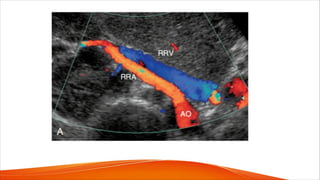

• Each kidney receives its arterial supply from one or more renal arteries.

• Renal arteries arise from the proximal abdominal aorta a the level of L1-L2

just below the origin of the superior mesenteric artery, which serves as a

reference point

• The right renal artery arises anterolaterally from the aorta and passes

posterior to the inferior vena cava (IVC). It is the only major vessel that

courses posteriorly to the IVC.

• The left renal artery generally arises from the lateral or posterolateral aspect

of the aorta. Anterior to each renal artery runs a corresponding renal vein,

and both vessels course anterior to the renal pelvis before entering the

medial aspect of the renal hilum

• The left renal vein lies between the superior mesenteric artery and the aorta.

• The right kidney is relatively inferior

to the left kidney, which explains the

downward course of the right renal

artery, traversing posterior to IVC

and right renal vein.

• The left renal artery arises below

the level of the right renal artery

origin and is more horizontally

oriented. It has a direct upward

course to the more superiorly

positioned left kidney.